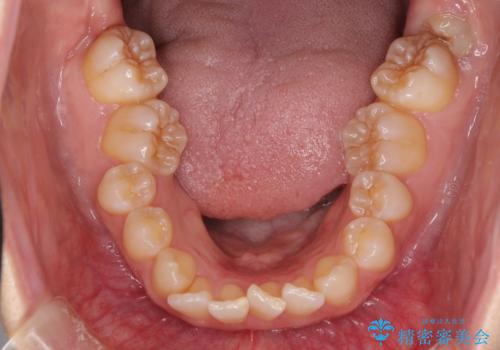

- 前歯のデコボコと奥歯の不正咬合を気にして来院された患者様です。

左右の大臼歯が全て鋏状咬合(シザーズバイト)になっており、治療が難航することが予想されましたが、インビザラインにより治療を行うこととしました。

最難関と思われたシザーズバイトは比較的短期間で解消されました。

しかし、治療中に2度の出産を経験され、治療期間は長くなってしまいましたが、咬みやすく、清掃しやすい歯列を獲得することができました。